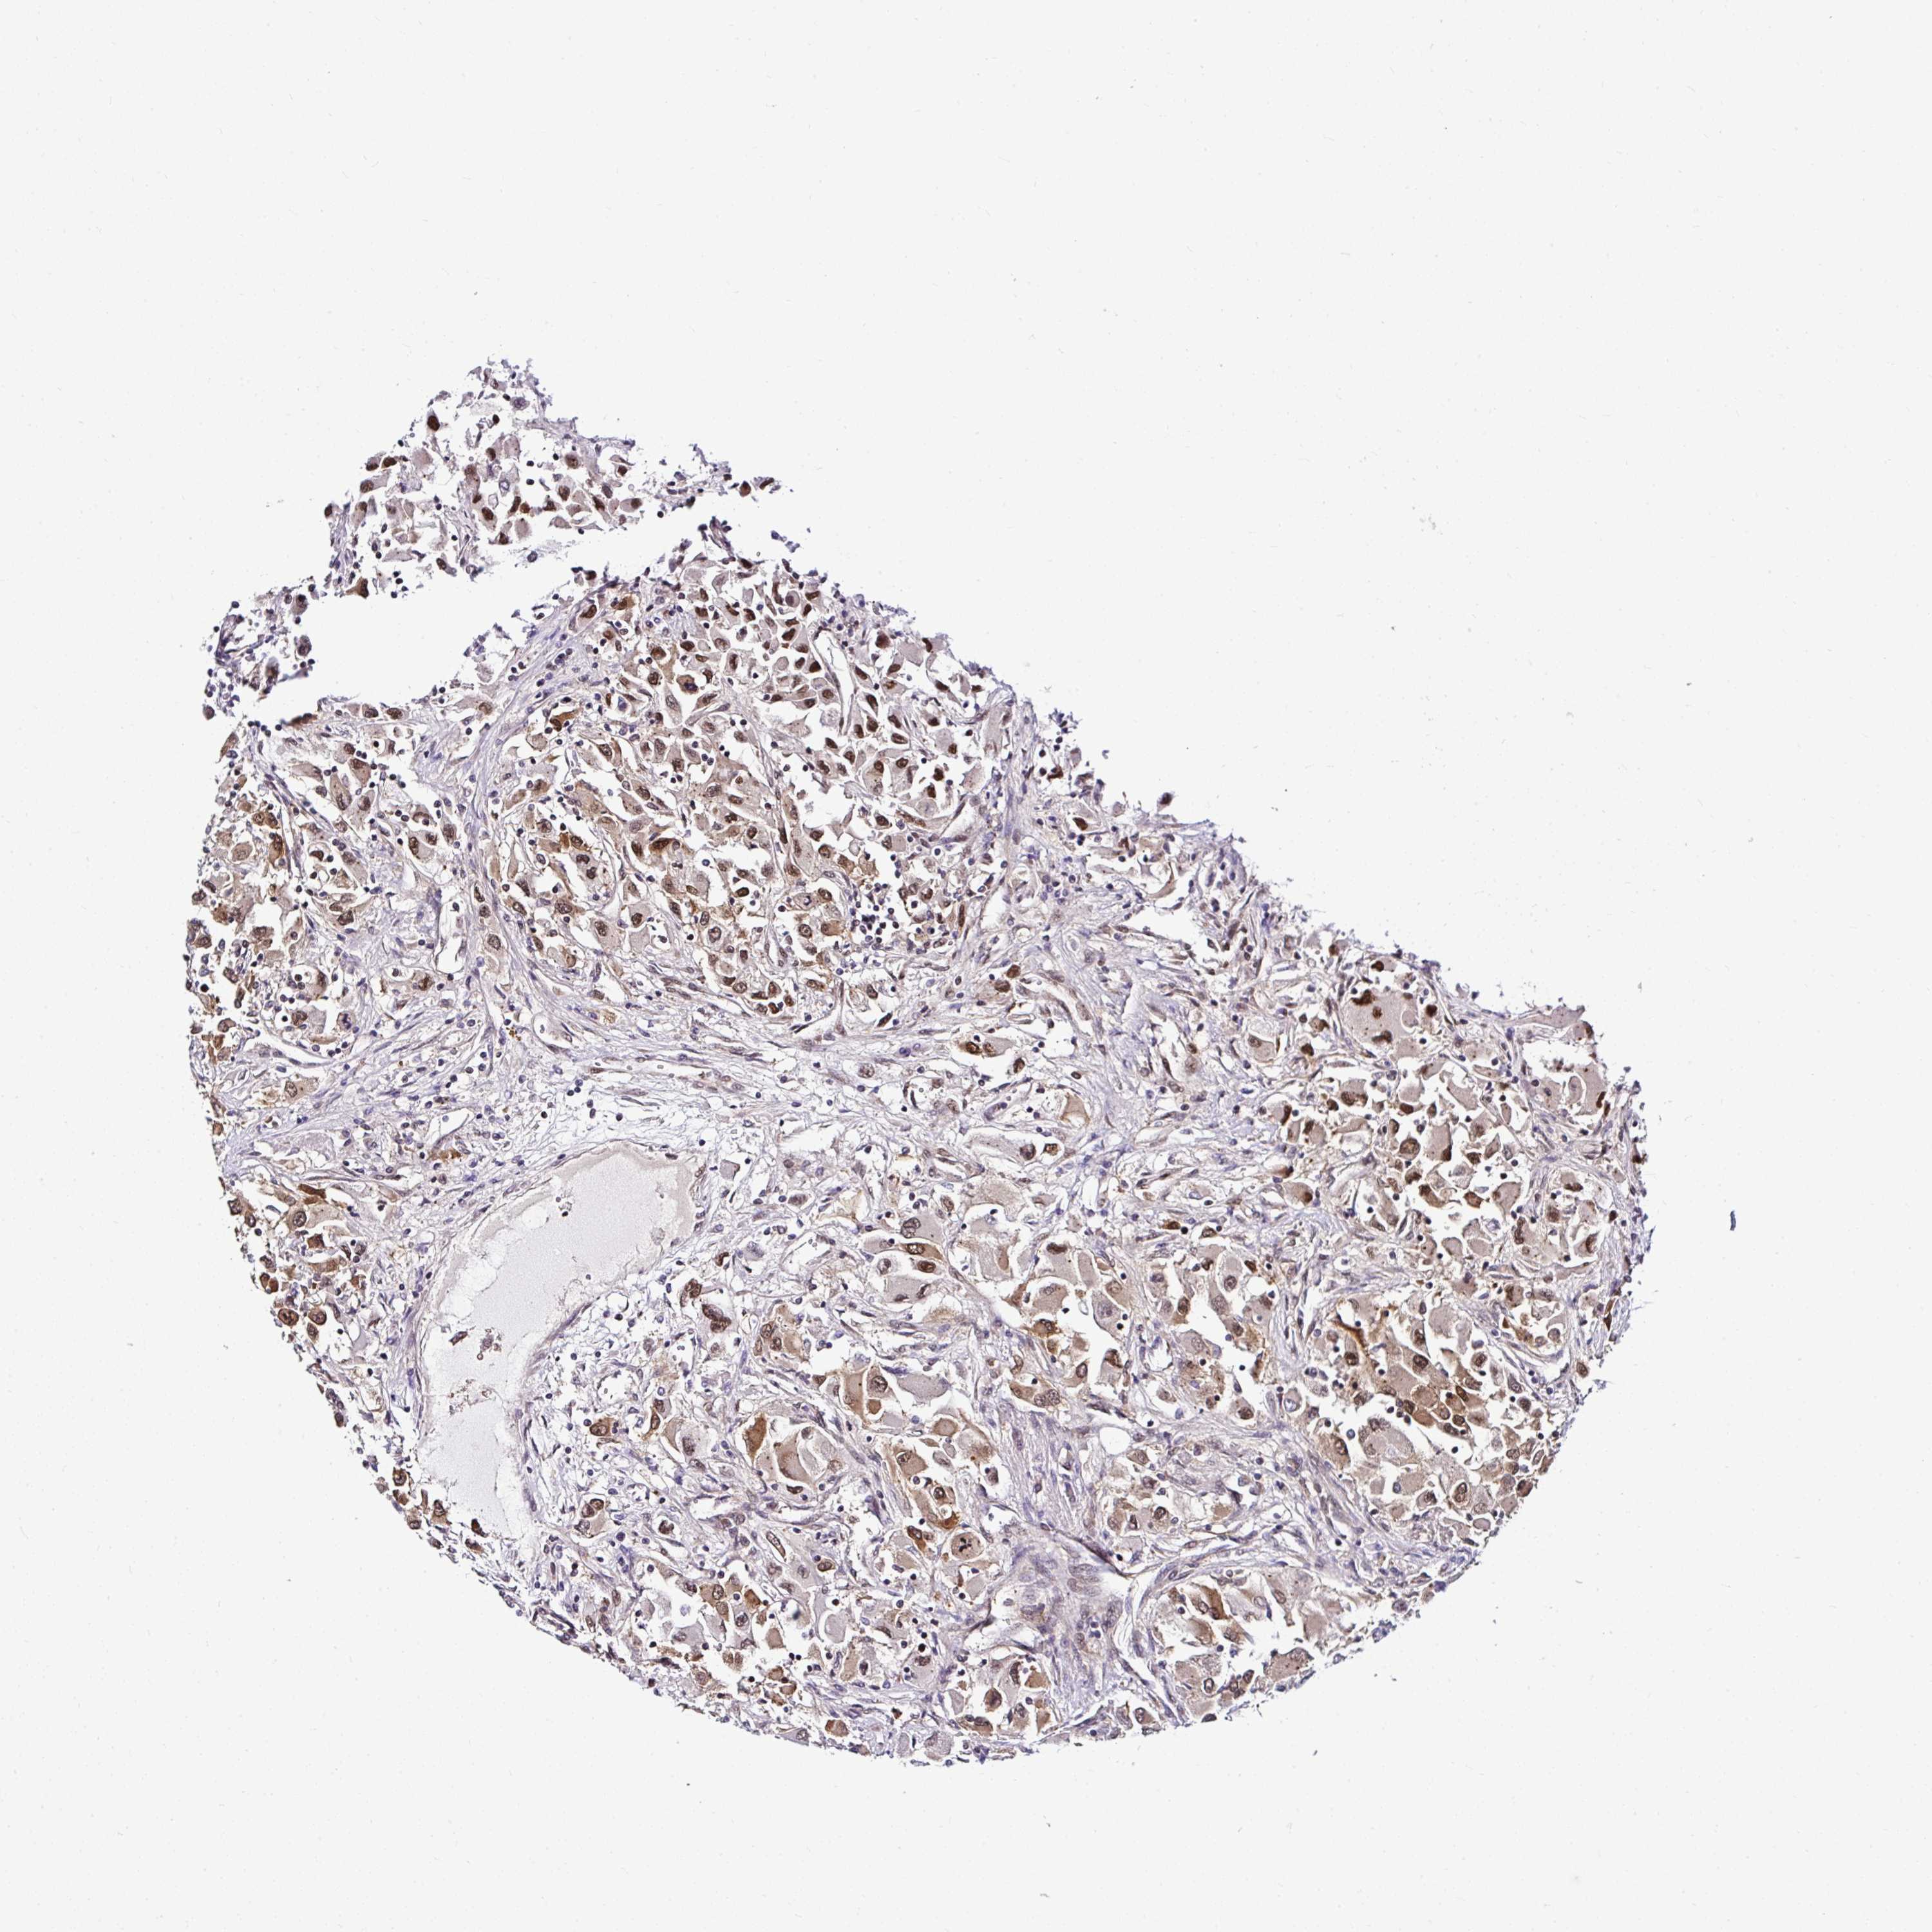

PIN4

KIDNEY RENAL CLEAR CELL CARCINOMA (VALIDATION) - Interactive survival scatter ploti

The Survival Scatter plot shows the clinical status (i.e. dead or alive) for all individuals in the patient cohort, based on the same data that underlies the corresponding Kaplan-Meier plots. Patients that are alive at last time for follow-up are shown in blue and patients who have died during the study are shown in red.

The x-axis shows the expression levels (FPKM) of the investigated gene in the tumor tissue at the time of diagnosis. The y-axis shows the follow-up time after diagnosis (years). Both axes are complimented with kernel density curves demonstrating the data density over the axes. The top density plot shows the expression levels (FPKM) distribution among dead (red) and alive patients (blue). The right density plot shows the data density of the survived years of dead patients with high and low expression levels respectively, stratified using the cutoff indicated by the vertical dashed line through the Survival Scatter plot. This cutoff is automatically defined based on the FPKM cutoff that minimizes the p-score. The cutoff can be changed by dragging the vertical line or by entering a cutoff value in the square labeled "Current cut-off".

Under the Survival Scatter plot the p-score landscape (black curve; left axis) is shown together with dead median separation (red curve; right axis). Dead median separation is the difference in median mRNA expression between patients who have died with high and low expression, respectively. It is calculated as follows: median FPKM expression of dead patients with high expression - median FPKM expression of dead patients with low expression. This is intended to aid the user in visually exploring custom cutoffs and the associated p-scores and dead median separation.

Individual patient data is displayed and can be filtered by clicking on one or more of the category buttons on the top of the page. Categories describing expression level and patient information include: high, low, alive, dead, female, male and tumor stages. The scale of the x-axis can be toggled between linear and log-scale by clicking on the "x log" button. Mouse-over function shows TCGA ID, patient information and mRNA expression (FPKM) for each patient.

& Survival analysisi

Kaplan-Meier plots summarize results from analysis of correlation between mRNA expression level and patient survival. Patients were divided based on level of expression into one of the two groups "low" (under cut off) or "high" (over cut off). X-axis shows time for survival (years) and y-axis shows the probability of survival, where 1.0 corresponds to 100 percent.

PIN4 is not prognostic in Kidney Renal Clear Cell Carcinoma (validation)

Best expression cut offi

Based on the FPKM value of each gene, patients were classified into two groups and association between prognosis (survival) and gene expression (FPKM) was examined. The best expression cut-off refers the FPKM value that yields maximal difference with regard to survival between the two groups at the lowest log-rank P-value. Best expression cut-off was selected based on survival analysis .

When clicking on this number, the vertical dashed line indicating cut-off, the interactive survival plot, and the Kaplan-Meier curve will be adjusted to show results based on the best expression cut-off.

: 20.92

TCGA RNA samplesi

RNA-seq data is reported as average FPKM (number Fragments Per Kilobase of exon per Million reads), generated by the The Cancer Genome Atlas (TCGA) .

Normal distribution across the dataset is visualized with box plots, shown as median and 25th and 75th percentiles. Points are displayed as outliers if they are above or below 1.5 times the interquartile range. FPKM values of the individual samples are presented next to the box plot.

Average pTPM 20.7

Number of samples 100